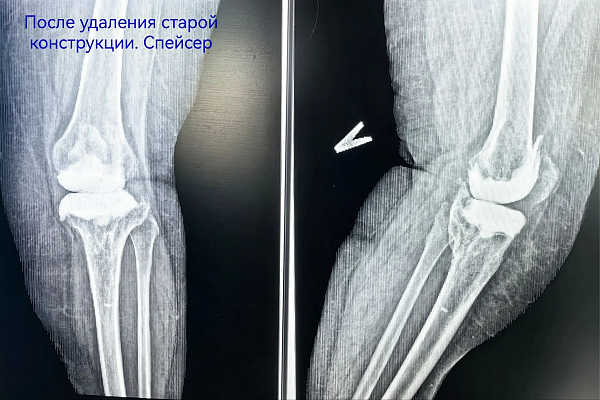

Лечение началось с санации очага воспаления - пациентке имплантировали временный антибактериальный спейсер. Параллельно начали подготовку к следующему этапу – ревизионному эндопротезированию.

Разрушенный инфекцией фрагмент большеберцовой кости требовал замещения. Чтобы восполнить её целостность, обратились к производителям 3D-протезов. На основе данных компьютерной томографии специалисты изготовили точную копию утраченного костного фрагмента. Операция по его установке и эндопротезированию сустава прошла успешно. Пациентка уже выписана и настроена на возвращение к полноценной активности.